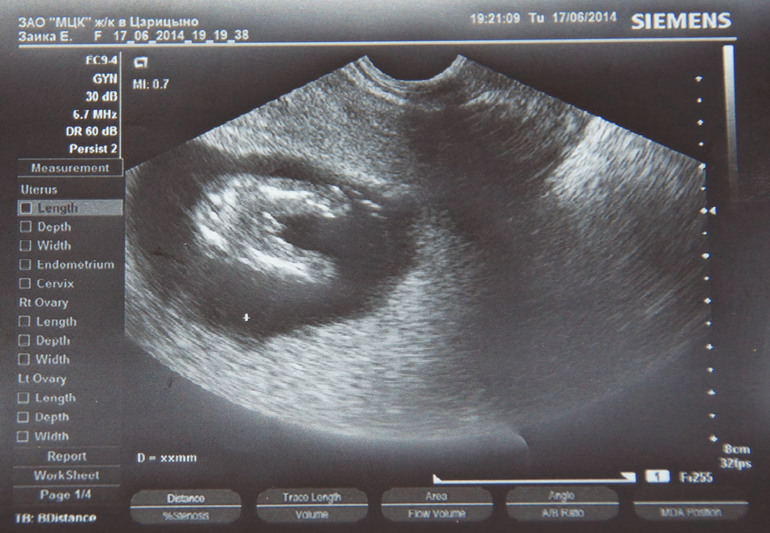

Врач сходу сказала, что мальчик, и потом со всех сторон и сама рассматривала и нам показывала. Но под конец посмеялась и решила пока принять 90%)))ну вот фото снизу, вид на попку, ножки и.... 838f68d60ead0f27a7c3e0700579344a.jpg

24.06.2014

Удачный ракурс))) Мальчик для вас, наверное, будет очень долгожданным)))

25.06.2014

))) Я бы не сказала big_smiles_162.gif Скорее — полная неожиданность!